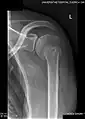

X-ray at left shows anterior dislocation in a young man after trying to get up from his bed. X-ray at right shows same shoulder after reduction and internal rotation, revealing both a bony Bankart lesion and a Hill-Sachs lesion. -